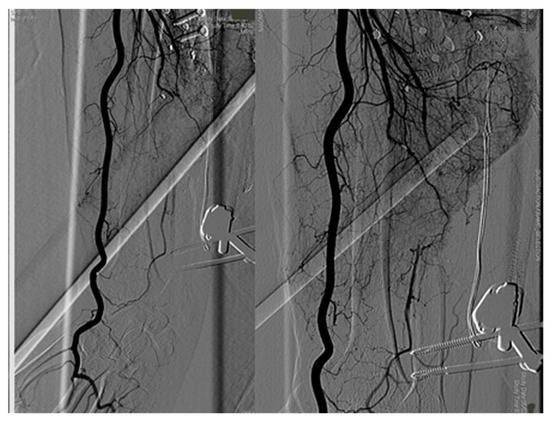

The posterior tibial artery was compromised. To avoid ischemic damage to the lower limb, we planned soft tissue coverage with latissimus dorsi free flap using a two-stage AVL technique. Initially, we harvested the great saphenous vein from the contralateral leg. AVL was performed on the femoral vein and artery, 10 cm above the knee (Figure 10).

Figure 10. First stage of AVL technique, great saphenous vein harvested from contralateral legand attached end-to-side to femoral artery and vein.